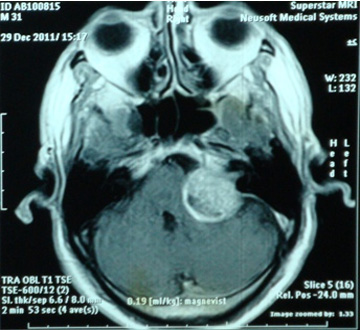

تومور در فضای بین مغز و گوش که زاویه پلی مخچه نامیده می شود، ایجاد می شود. آکوستیک نورما جزء تومورهای خوش خیم است اما خطر این تومور به دلیل رشد آن در فضای حساس و فشار آوردن آن به ساختارهای حیاتی مانند اعصاب جمجمه، مغز و ساقه مغز است. شایع ترین نشانه تومور شامل کاهش شنوائی در گوش مبتلا، وزوز گوش و عدم تعادل می باشد. برای به دست آوردن بهترین نتیجه، تشخیص صحیح به منظور انتخاب بهترین روش درمان در این مشکل است. برای تشخیص نورینوم آکوستیک ام آر آی توصیه می شود. این روش تصویر برداری نه تنها به تشخیص کمک می کند بلکه می کند وسعت و عوارض احتمالی مانند هیدروسفالی را مشخص می کند.

نمونه های زیر MRI پزشک متخصصی است که توسط اصغری جراحی شده اند: